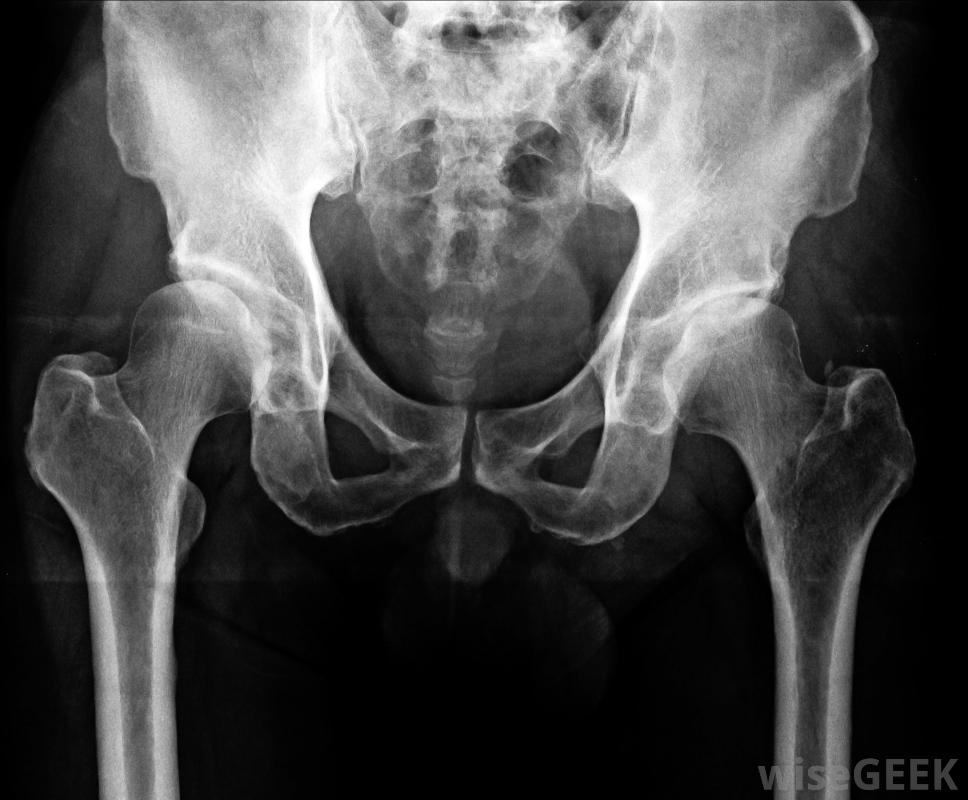

半骨盆切除術是一種外科手術,其中一條腿和一部分骨盆被切除。半骨盆切除術的范圍可能會有所不同,有些手術需要切除一半的骨盆,而另一些手術則需要切除少于一半的骨盆。這種手術對病人來說是非常創傷的,是最后的治療手段;換言之,當外科醫生建議進行半骨盆切除術時,他或她認為這對患者是必要的。

最罕見的截肢。病人通常會因為癌癥而接受半骨盆切除術,而癌癥是無法用其他方法治療的,或者是因為外傷性事故,如工廠地板上的擠壓傷或嚴重的車禍。在創傷性半骨盆切除術中,病人的骨盆和腿部可能已經嚴重受損,以至于外科醫生認為它們無法重新連接,患者最好截肢并避免感染的風險。

在某些情況下,外科醫生可以進行內部半骨盆切除術,也就是所謂的"保肢"手術。在這種情況下,部分骨盆被切除,但肢體完好無損,外科醫生可以植入人工關節或假體。手術后患者的功能水平可能會有所不同,有些病人的肢體完全喪失了功能,而另一些病人可能還能保留一些功能,外科醫生也需要監控這個部位,以防需要進行完全截肢

,兩個肢體都被切除。另一個被稱為髖關節離斷的手術,包括在髖關節處完全切除腿部,骨盆保持完整。在某些情況下,髖關節的一部分可能會留在原位以保持穩定或舒適。這種手術對患者來說也是非常創傷的,需要很長的恢復時間。